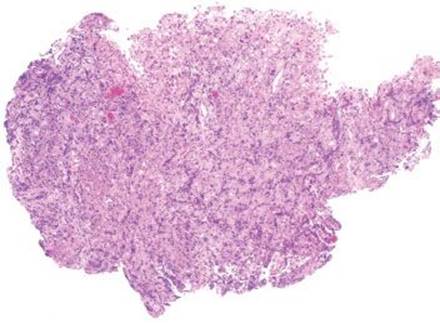

Endoscopic images of cytomegalovirus infection (CMV) are variable and can include normal, erythema, erosions, or ulcerations (Fig. 2.64).46 Similar to that seen with CMV infections of other sites, the characteristic inflammatory backdrop shows a prominence of mononuclear cells (lymphocytes, macrophages, lymphocytes, and plasma cells), increased apoptotic bodies, erosions, ulcers, and acute inflammation (Figs. 2.65 and 2.66). The classic viral cytopathic effect includes nuclear enlargement, prominent nuclear inclusions (with an “owls’ eye” appearance), and nuclear and or cytoplasmic inclusions (Fig. 2.67). These changes are predominantly seen in stromal and endothelial cells; hence, biopsy of the ulcer base is critical for complete evaluation. Often times, viral cytopathic effect in the stomach is sneaky and may only include scattered enlarged cells with slightly smudged chromatin and prominent apoptotic bodies (Figs. 2.68 and 2.69). Unlike in other sites, CMV gastritis (and enteritis) can feature viral cytopathic effect in epithelial cells, although the key features are generally very subtle (Fig. 2.70). As these features can also be seen in regenerative atypia, a low threshold for a CMV immunostain is worthwhile. Importantly, sometimes the only clue to CMV gastritis is prominent foveolar hyperplasia reminiscent of a gastric hyperplastic polyp (Figs. 2.71–2.75).47,48This pattern is particularly common in immunocompromised individuals and can be seen with a complete lack of acute and chronic inflammation. See also Hyperplasia Pattern, this chapter.

Figure 2.65 Acute gastritis pattern, CMV. Like that in any other site, the characteristic inflammatory backdrop of CMV infection includes a prominence of mononuclear inflammation, composed of lymphocytes, macrophages, lymphocytes, and plasma cells, in addition to acute inflammation. Whenever this pattern is seen, careful examination for CMV is required; a CMV immunostain is recommended if diagnostic cells are not apparent on H&E.

Figure 2.66 Acute gastritis pattern, CMV. Higher power of previous case (Fig. 2.65). CMV infected cells were detected with CMV immunostain (not shown).